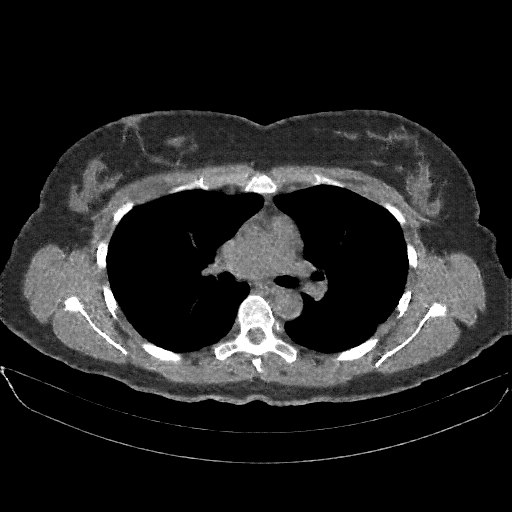

Targeted Slice 70 - Mediastinum Window Analysis (Generated vs Real Venous)

0.741

Mediastinum SSIM

34.8

Mediastinum RMSE

13.6

Mediastinum MAE

Average Mediastinum Window Metrics Across All Slices (38 slices) - Generated vs Real Venous

0.727

Mediastinum SSIM (Avg)

35.7

Mediastinum RMSE (Avg)

14.6

Mediastinum MAE (Avg)

Reconstructed NATIVE CT scan (cycle consistency)

No window - Raw intensity values

Mediastinum window (WL 40, WW 400 β†’ Low βˆ’160, High +240)